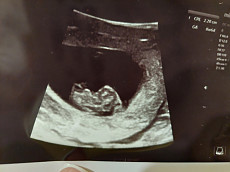

- Nėštumas